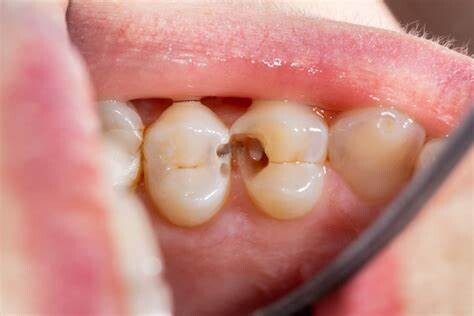

You know the importance of brushing your teeth and having good oral hygiene to avoid cavities. But did you know that cavities aren't just in your teeth?

Yes, even when you take care of your enamel, you can still end up with a cavity between your teeth. This has a technical term called an interproximal cavity. It forms like other cavities: when the enamel is worn away and bacteria are able to get into the tooth.

When this happens with your permanent teeth, it can cause tooth pain that you don't want to have to deal with, as well as other problems when the cavity penetrates into the bloodstream.

A cavity is an easily preventable dental condition in which the hard surface of your teeth (the enamel) ends up with a tiny hole in it. This permanent damage is caused when the bacteria stick to the tooth.

As you engage in frequent snacking, eat sugary foods or drink sugary drinks, and don't effectively clean right after, the food particles form dental plaque.

As plaque, bacteria sticks to the enamel and decays the tooth. If you don't remove decay fast, it turns into a hole that requires a large filling to fix it. However, if it's caught early, the enamel could be recalcified with fluoride gel.